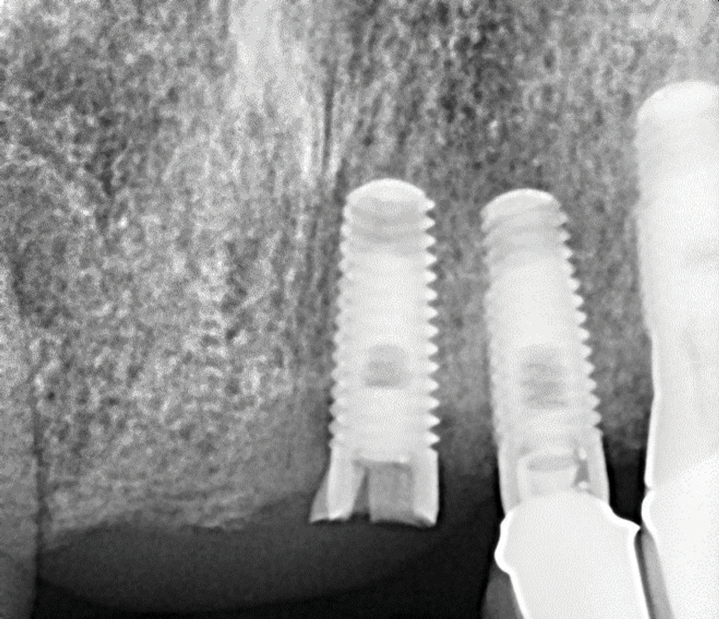

Implants with internal hex connections are more prone to failure at the connection than those with external hex connections.28 This is related to the thickness of the metal at the thinnest point between the internal surface of the interface and the external surface at the crestal area of the implant. When overloaded, implants with an internal hex connection may present with fractures at the points of the hex.29 These points are where the metal is the thinnest at the crestal portion of the implant and where stress is concentrated during overloading. This is less problematic in wider diameter implants because the metal is thicker in this area of the implant; however, in standard or narrow diameter implants, fracture may result, causing catastrophic failure of the implant (Figure 1). This may also occur in other internal implant connection types, such as trilobe connections, especially when the crestal thickness of the implant is minimal, leading to fracture of the coronal aspect of the implant (Figure 2). Implants with conical connections are not immune to potential fracture in this area, and the thin walls of some standard or narrow diameter models may split even without the isolated stress points observed in internal hex-, trilobe-, and octagon-type connections (Figure 3).30 Sometimes, fractures of implants at the coronal aspect are not clinically visible but, instead, are identified radiographically either after a patient complaint of pain in the area, due to the presence of soft-tissue inflammation, or during a routine examination with no patient complaint (Figure 4).

(2.) Fracture of the coronal portion of the trilobe connection of a standard diameter implant fabricated from CP-Ti grade 4 related to mechanical overloading.

Figure 2